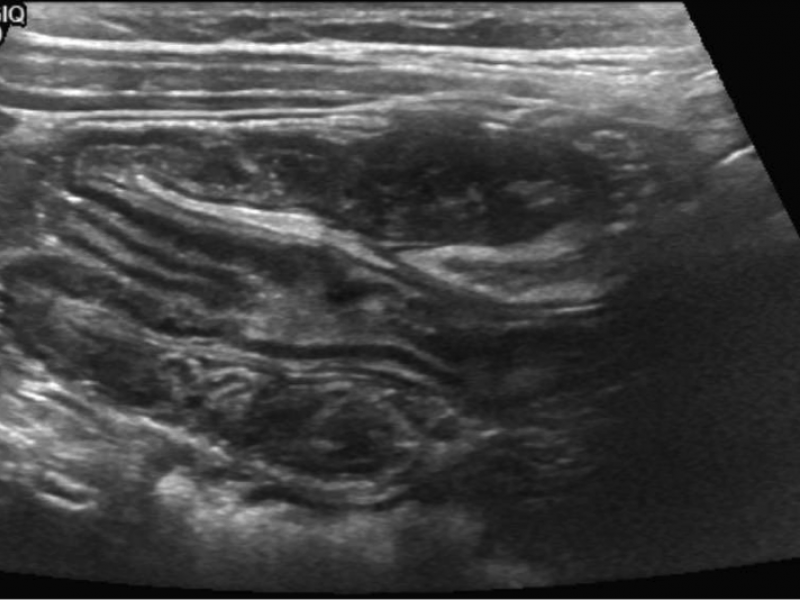

Answer: B) Air or water-soluble contrast enema Diagnosis

Case: A 2 year-old male with no significant PMH is brought